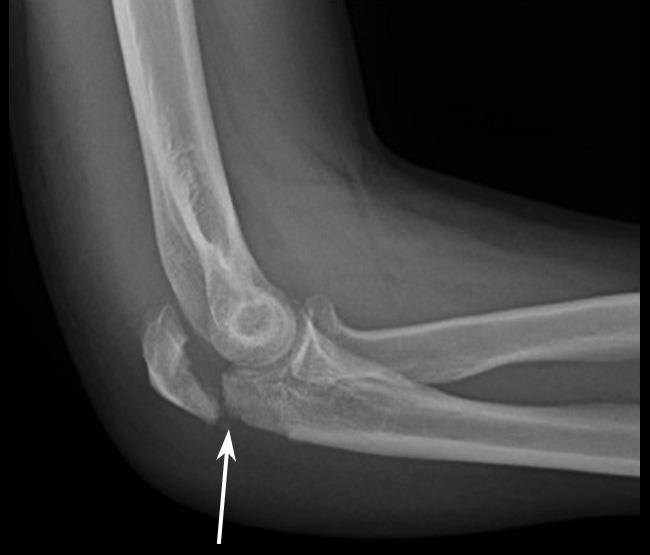

The elbow is a hinge type joint that is formed of the humerus (the bone of the upper arm), the radius and the ulna. Together they form three articulations at the elbow:

Lastly, like any body part, the joint can be at risk of a fracture, particularly when the natural reaction when we fall is to put our hands out. As a result of immobilisation following an injury, the tissues can become stiff and range of movement reduced and therefore early rehabilitation is crucial.